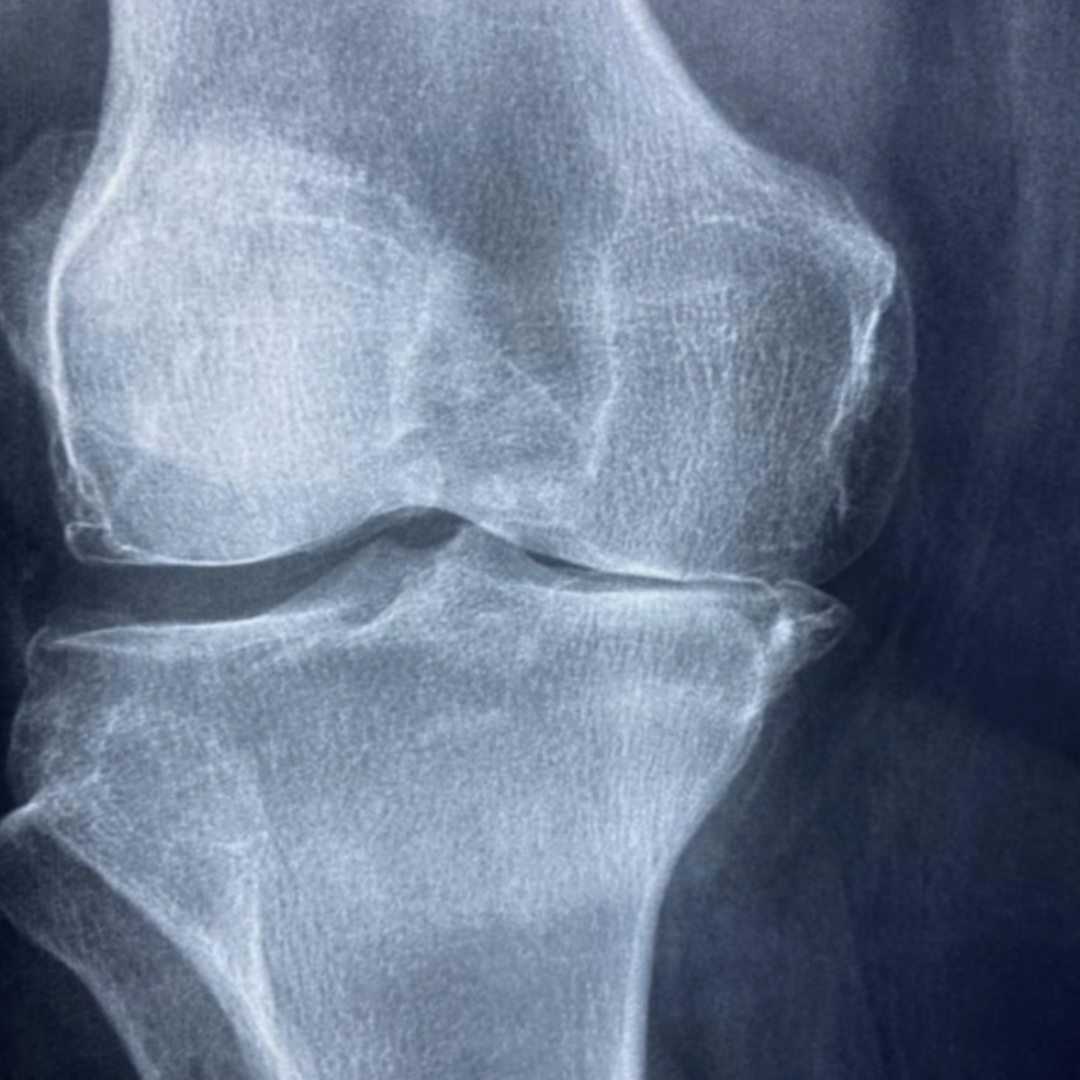

우리 몸의 뼈와 뼈 사이에는 '연골'이라는 조직이 있어요. 마치 뼈 사이의 쿠션처럼, 움직임을 부드럽게 하고 충격을 흡수하는 역할을 하죠. 연골 덕분에 우리는 아프지 않고 자유롭게 움직일 수 있는 거예요.

하지만 연골은 한 번 손상되면 재생이 어렵다는 사실! 그래서 평소에 연골 건강을 잘 지켜주는 것이 매우 중요해요. 특히 나이가 들수록 연골은 점점 닳고 약해지기 때문에 더욱 신경 써야 한답니다.

연골이 건강해야 관절염과 같은 질환을 예방하고, 활기찬 일상을 오래도록 유지할 수 있어요.